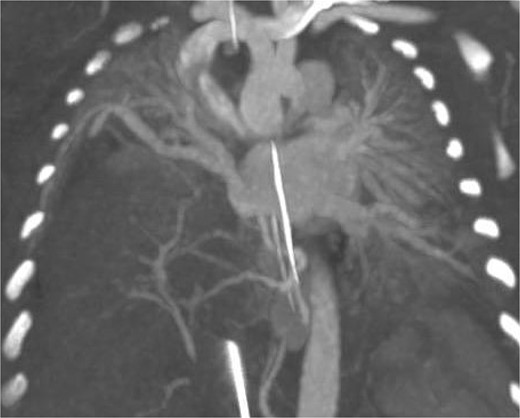

Postoperatively the patient developed worsening pulmonary hypertension and was started on milrinone. Subsequent imaging included an MRI which demonstrated a right sided CDH and a portion of the right hepatic lobe in the chest. Because of difficulty differentiating the vasculature on MRI, a CTA was performed confirming the presence of the HPF with a right sided intra-lobar sequestration and a single right pulmonary vein (Fig. 2).

CT arteriography: coronal slice demonstrating anatomy of pulmonary veins with two left sided pulmonary veins draining into the left atrium and the single right sided upper pulmonary vein also draining into the left atrium.